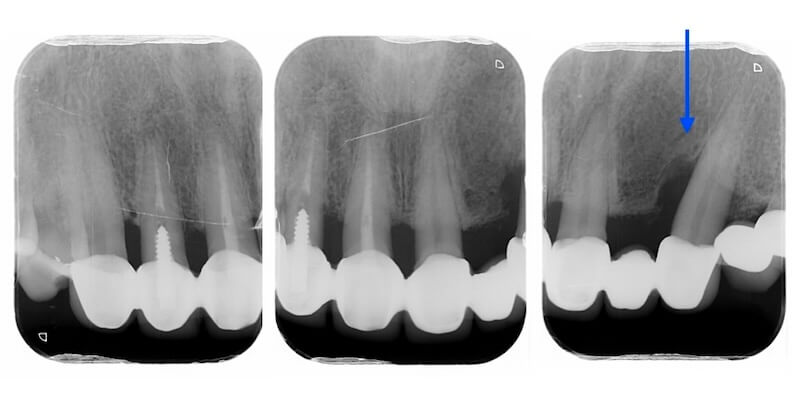

經過全口初步檢查以及X光片的檢查,我的診斷是全口中度慢性牙周病。治療牙周病過程中我會搭配顯微鏡和水雷射,也就是『顯微水雷射牙周病治療』。不過在牙周治療前,我們也要先把上述的兩個會加重牙周病的問題一併考量,治療才會有效果。

Ms.H 是屬於第一種並且血壓已控制良好的高血壓患者。因此我們會在拆除她的舊假牙之後再開始進行全口牙周治療。拆除假牙後發現右上的側門齒是齒質不足的殘留牙根,因此預計在之後治療牙周病時同時拔除該患齒。

拆除舊假牙:釐清殘留牙根與齒質狀況

拆除舊假牙換上臨時假牙之後,開始進入牙周病的療程。我們會先將治療前口內狀況完整記錄,詳細分析每一顆牙齒的牙周狀況。